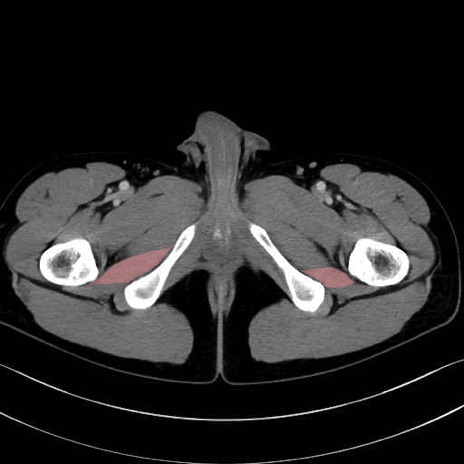

外閉鎖筋(obturator externus) のCT画像の解剖

外閉鎖筋 (Obturator externus)